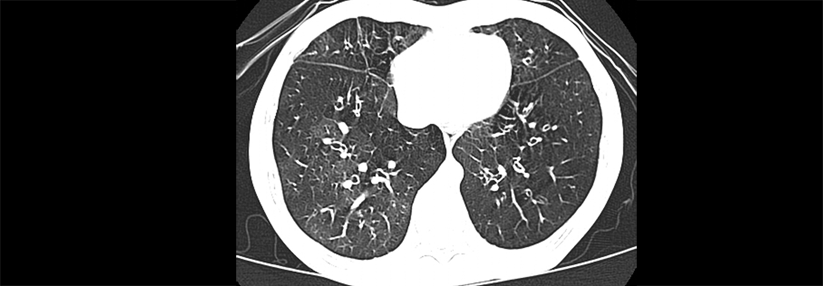

Mittlerweile kann die MRD mittels Next Generation Sequencing (NGS) bestimmt werden. Mittlerweile kann die MRD mittels Next Generation Sequencing (NGS) bestimmt werden. © iStock/koto_feja